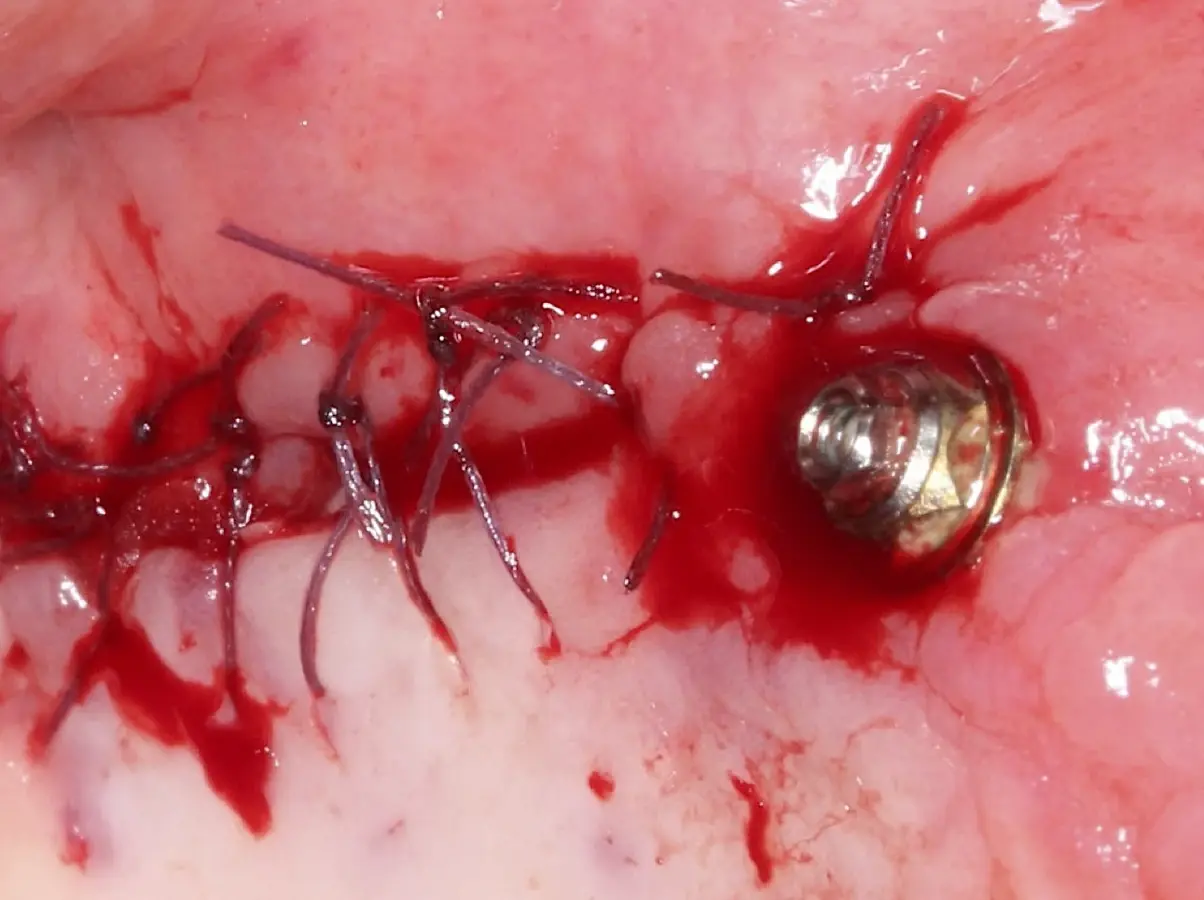

Se inicia la elevación de la membrana de Schneider con el inserto redondeado no cortante en forma de disco, empleando movimientos suaves. El levantamiento puede complementarse con elevadores convencionales, siguiendo la dirección mesiodistal. La fase de desprendimiento inicia con el piso y sigue hacia la pared mesial para terminar, y de ser necesario, hacia la pared posterior. Existen diversos insertos con angulaciones y longitudes para mayor accesibilidad16 (Figura 1).

El clínico puede retirar la tabla ósea o introducirla como “tienda de campaña” dentro del seno maxilar. En cualquiera de las alternativas, es importante evaluar la presencia de tabiques óseos y de la arteria postero alveolar superior.